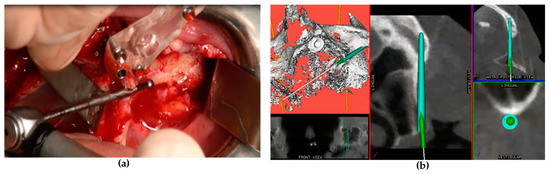

2.3. Surgical Procedure

Following general anesthesia and local infiltration of articaine with adrenaline (1:100.000), a mid-crestal incision was made at the level of the alveolar ridge keratinized mucosa with two oblique distal incisions at the level of the maxillary tuberosity. A mucoperiosteal flap was raised to expose the alveolar crest, lateral maxillary wall, pyriform aperture, infraorbital foramen, lateral orbital border, and zygomatic bone. A series of drills mounted on a straight or an angled handpiece (Figure 1a) and an implant motor (Surgysonic® Moto, Esacrom, Imola, Italy) were used to penetrate the alveolar process and the zygomatic bone according to the proposed implant diameter. In some cases, the initial steps were performed using an ultrasonic instrument. The zygomatic implant trajectory was verified in real time by using the ImplaNav dynamic navigation system (Figure 1b) with an intraoral reference tool.

Figure 1. Implant site preparation with the drill mounted on the angled handpiece (a) and real-time tracking of the drill via the navigation system screen (b).